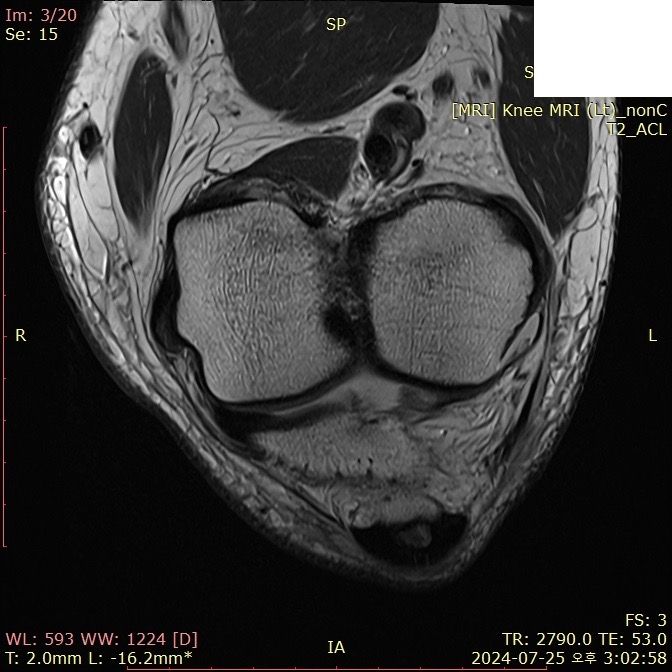

무릎 ACL(전방십자인대) 확인 부탁드려요

아스팔트에 무릎을 부딪쳐 심하게 부어서 mri 찍어봤는데 슬개골 비변위성 골절 판독 받은 건 기억 나는데, 인대는 기억이 잘 안나서 여쭤 봅니다..

전방십자인대 괜찮은가요...??ㅠㅠ